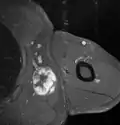

Histopathology of liposarcomas

Fig. 1 Micrograph of bone formation in a liposarcoma tumor -

Fig. 2 Micrograph of a dedifferentiated liposarcoma tumor -

Presentation

Dedifferentiated lipoosarcomas (DDL) occur most frequently in middle-aged and older adults with a peak incidence in their sixth to eighth decades.[8] Rarely, these tumors have developed in children and adolescents.[5] DDL tumors most commonly occur in the retroperitoneal space but, similar to ALT/WDL, may occur in the extremities, paratesticular area, mediastinum, head, or neck.[8] Less than 1% of all DDLs develop in superficial soft tissues[8] or the eye socket.[21] At presentation, DDL tumors typically are painless, large, may have been slowly and progressively enlarging for years,[8] and on routine X-rays contain areas of calcium deposition (exemplified by Fig. 1 in the Histopathology of liposarcomas section).[22][23] Less commonly, affected individuals have signs and/or symptoms due to their tumor's impingement on an organ (e.g. abdominal pain caused by blockage of the intestines or urinary tract obstruction caused by blockage of the urethra). Very rarely, individuals with DDL present with one or more signs or symptoms of chronic inflammation (see B symptoms) and/or one of the endrocrine, neurological, mucocutaneous, hematological, or other tissue-related paraneoplastic syndromes. The signs and symptoms of chronic inflammation and the various paraneoplastic syndromes are caused by the tumors' secretion of cytokines, hormones, prostaglandins, and/or other systemically acting agents; they completely disappear after the DDL is successfully treated.[8]

The histopathological appearance of DDL tumors (see Fig. 2 in the below Histopathology of liposarcomas section) varies widely but most frequently exhibits features of undifferentiated pleomorphic sarcomas (which are tumors densely populated with variably sized and shaped cells containing variability sized and shaped nuclei) or spindle cell sarcomas (which are tumors consisting of spindle-shaped cells in a connective tissue background). Different parts of DDL tumors often show variations in the appearances of their background connective tissues: these tissues may be myxoid (i.e. consisting of a clear, mucus-like substance which when stained using a standard H&E stain method appears more blue or purple than the red color of normal tissues) or myxocollagenous (i.e. high collagen fiber content in a myxoid background), and, in ~5% of cases, have areas of osteoid (see Fig. 1 in the below Histopathology of liposarcomas section) or cartilaginous material. The tumors also show large variations in their cell contents. For example, up to 10% of DDL tumors have areas with ALT/WDL histopathology [8] and rare cases of DDL have areas containing meningothelial-like whorls of flat cells.[24][25]